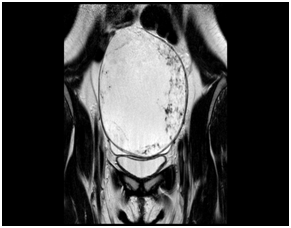

On physical examination, she had a non-tender mobile adnexal mass measuring 14cm, extending from the pelvis to the liver. Ultrasound examination revealed an adnexal mass measuring 150x101mm with thick septations but no papillary projections. Color Doppler was negative. There was no ascetic fluid seen. The serum levels of Cancer Antigen 153 (CA – 15.3), Carcinoembryonic Antigen (CEA) and Cancer Antigen 19.9 (CA 19.9) were within normal limits. Cancer Antigen 125 (CA – 125) serum levels were at 71.80. Magnetic resonance imaging (MRI) of the pelvis showed a mass lesion in the left pelvic region, measuring 142x93x125mm with multiple thick septations (Figure 1).

• Figure 1 MRI image of an enlarged left ovary. There are peripheral enlarged follicles.